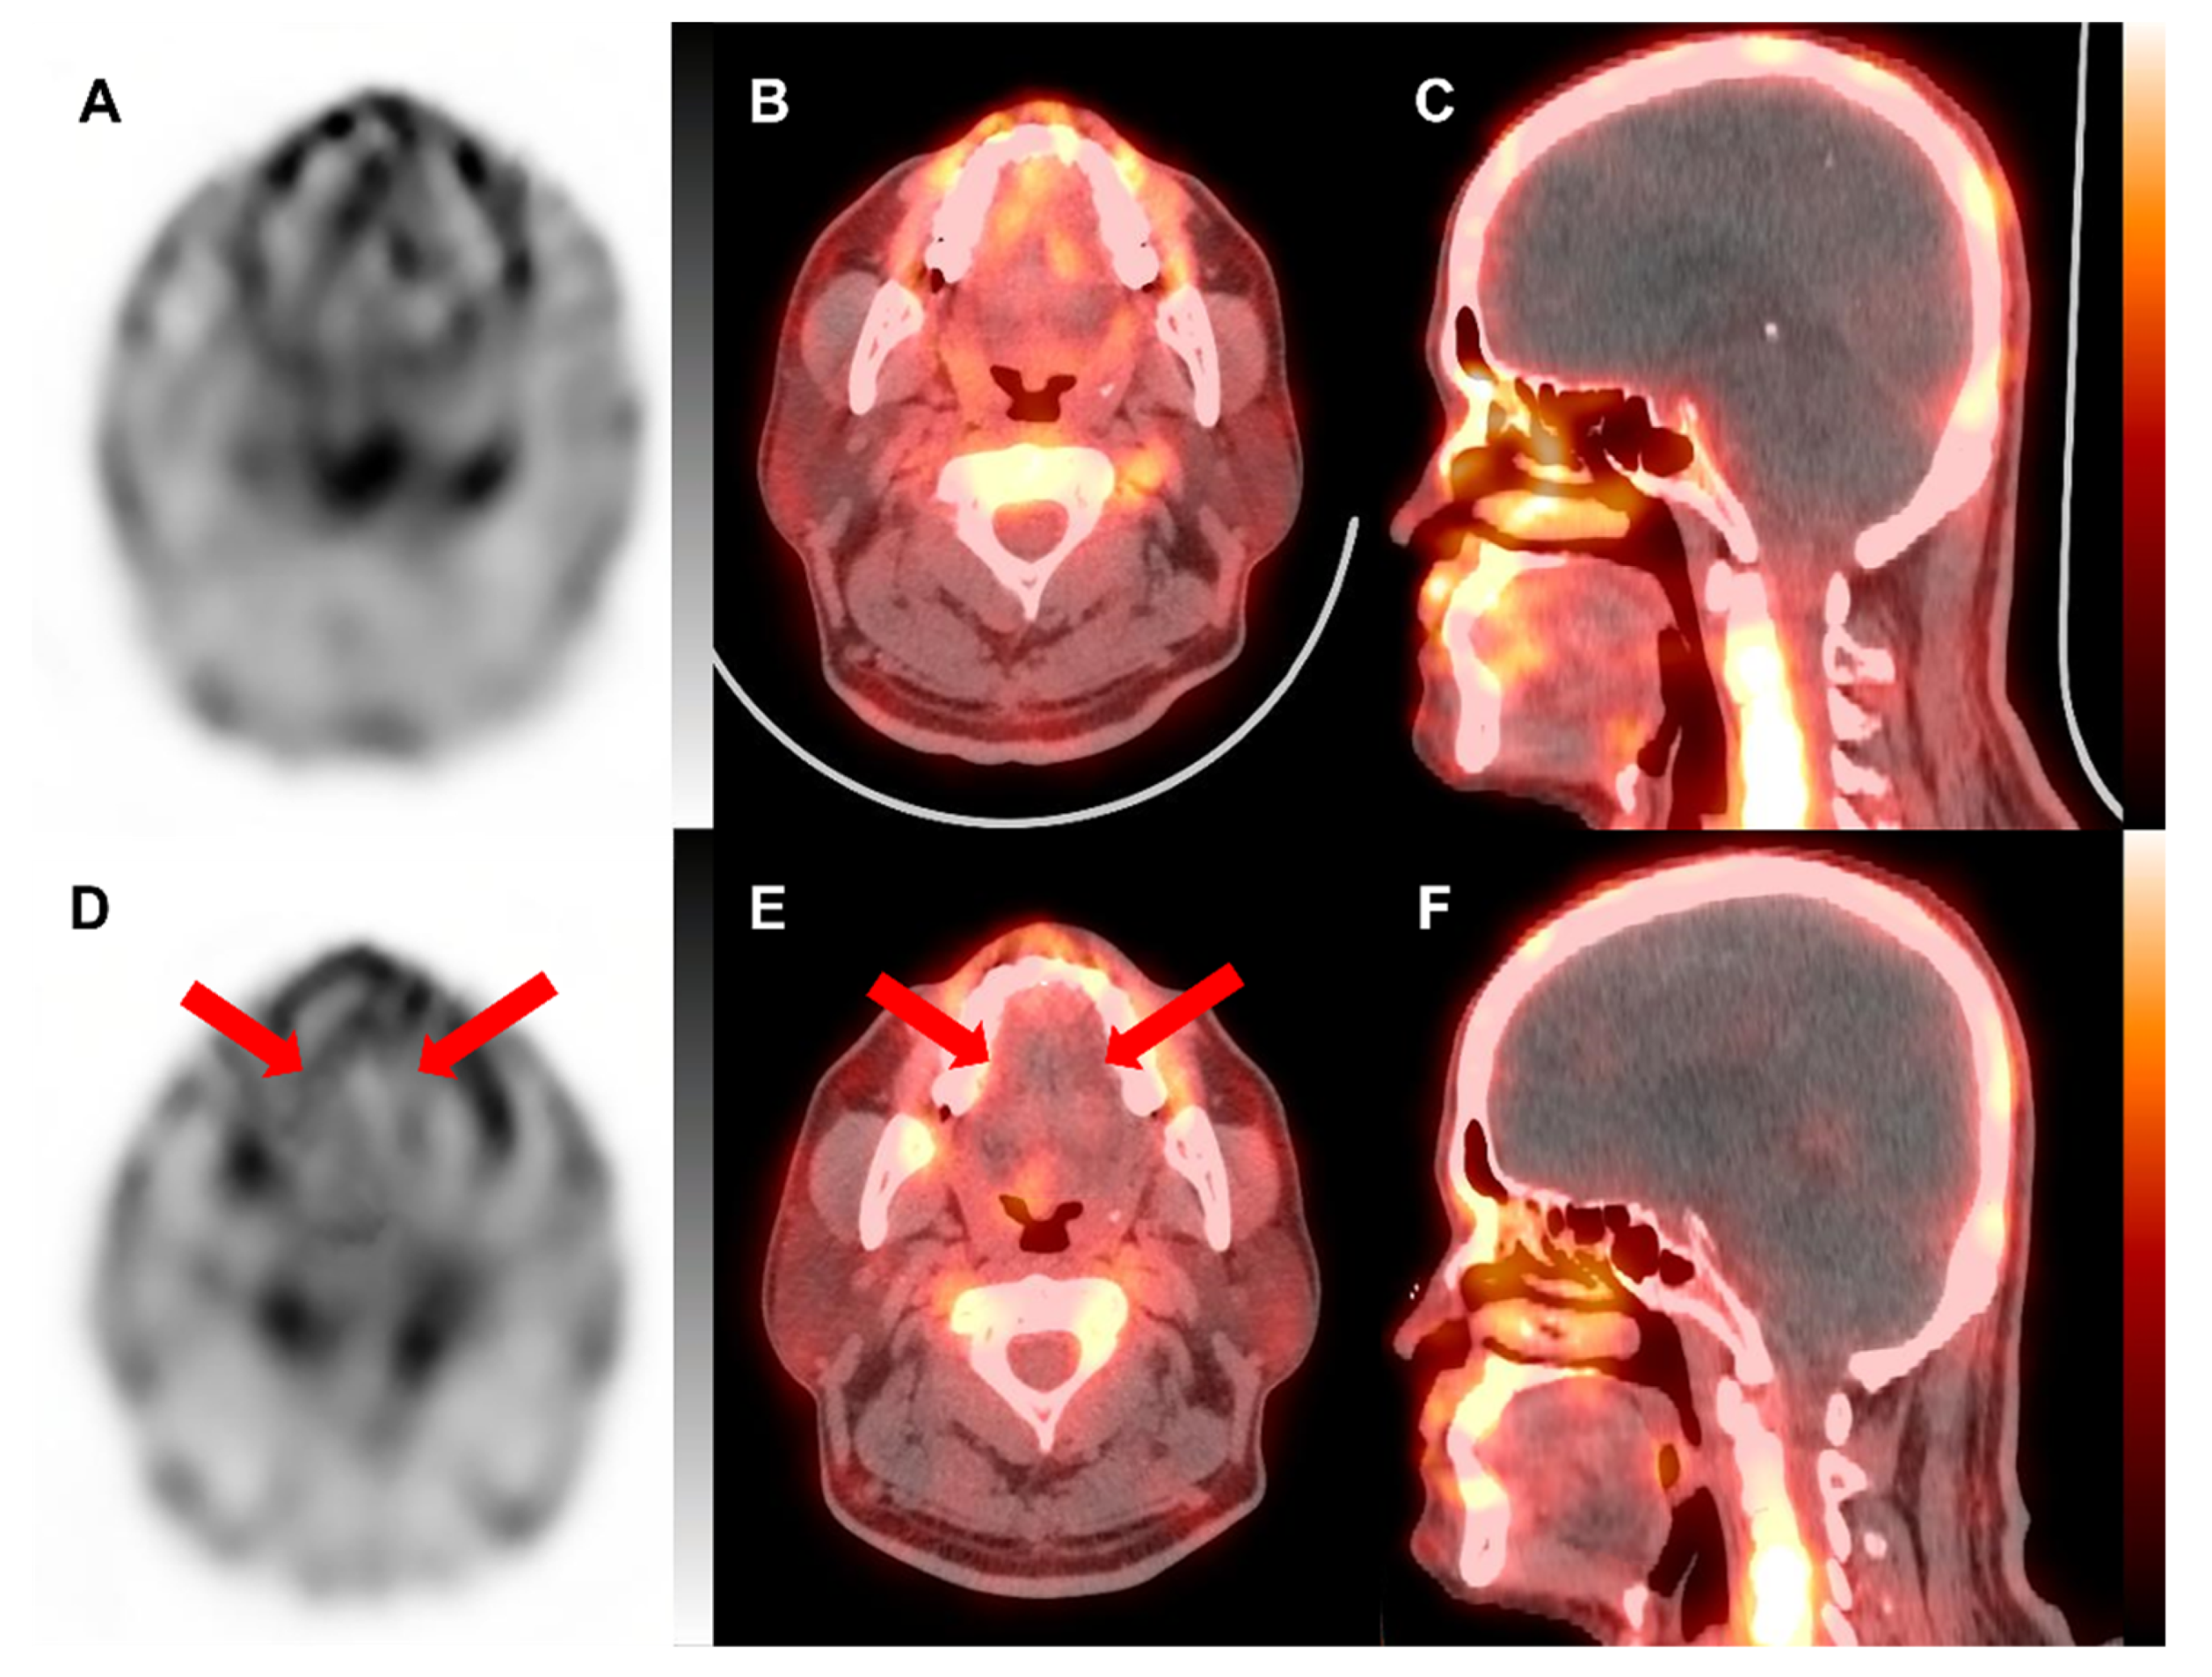

2. Case Presentation